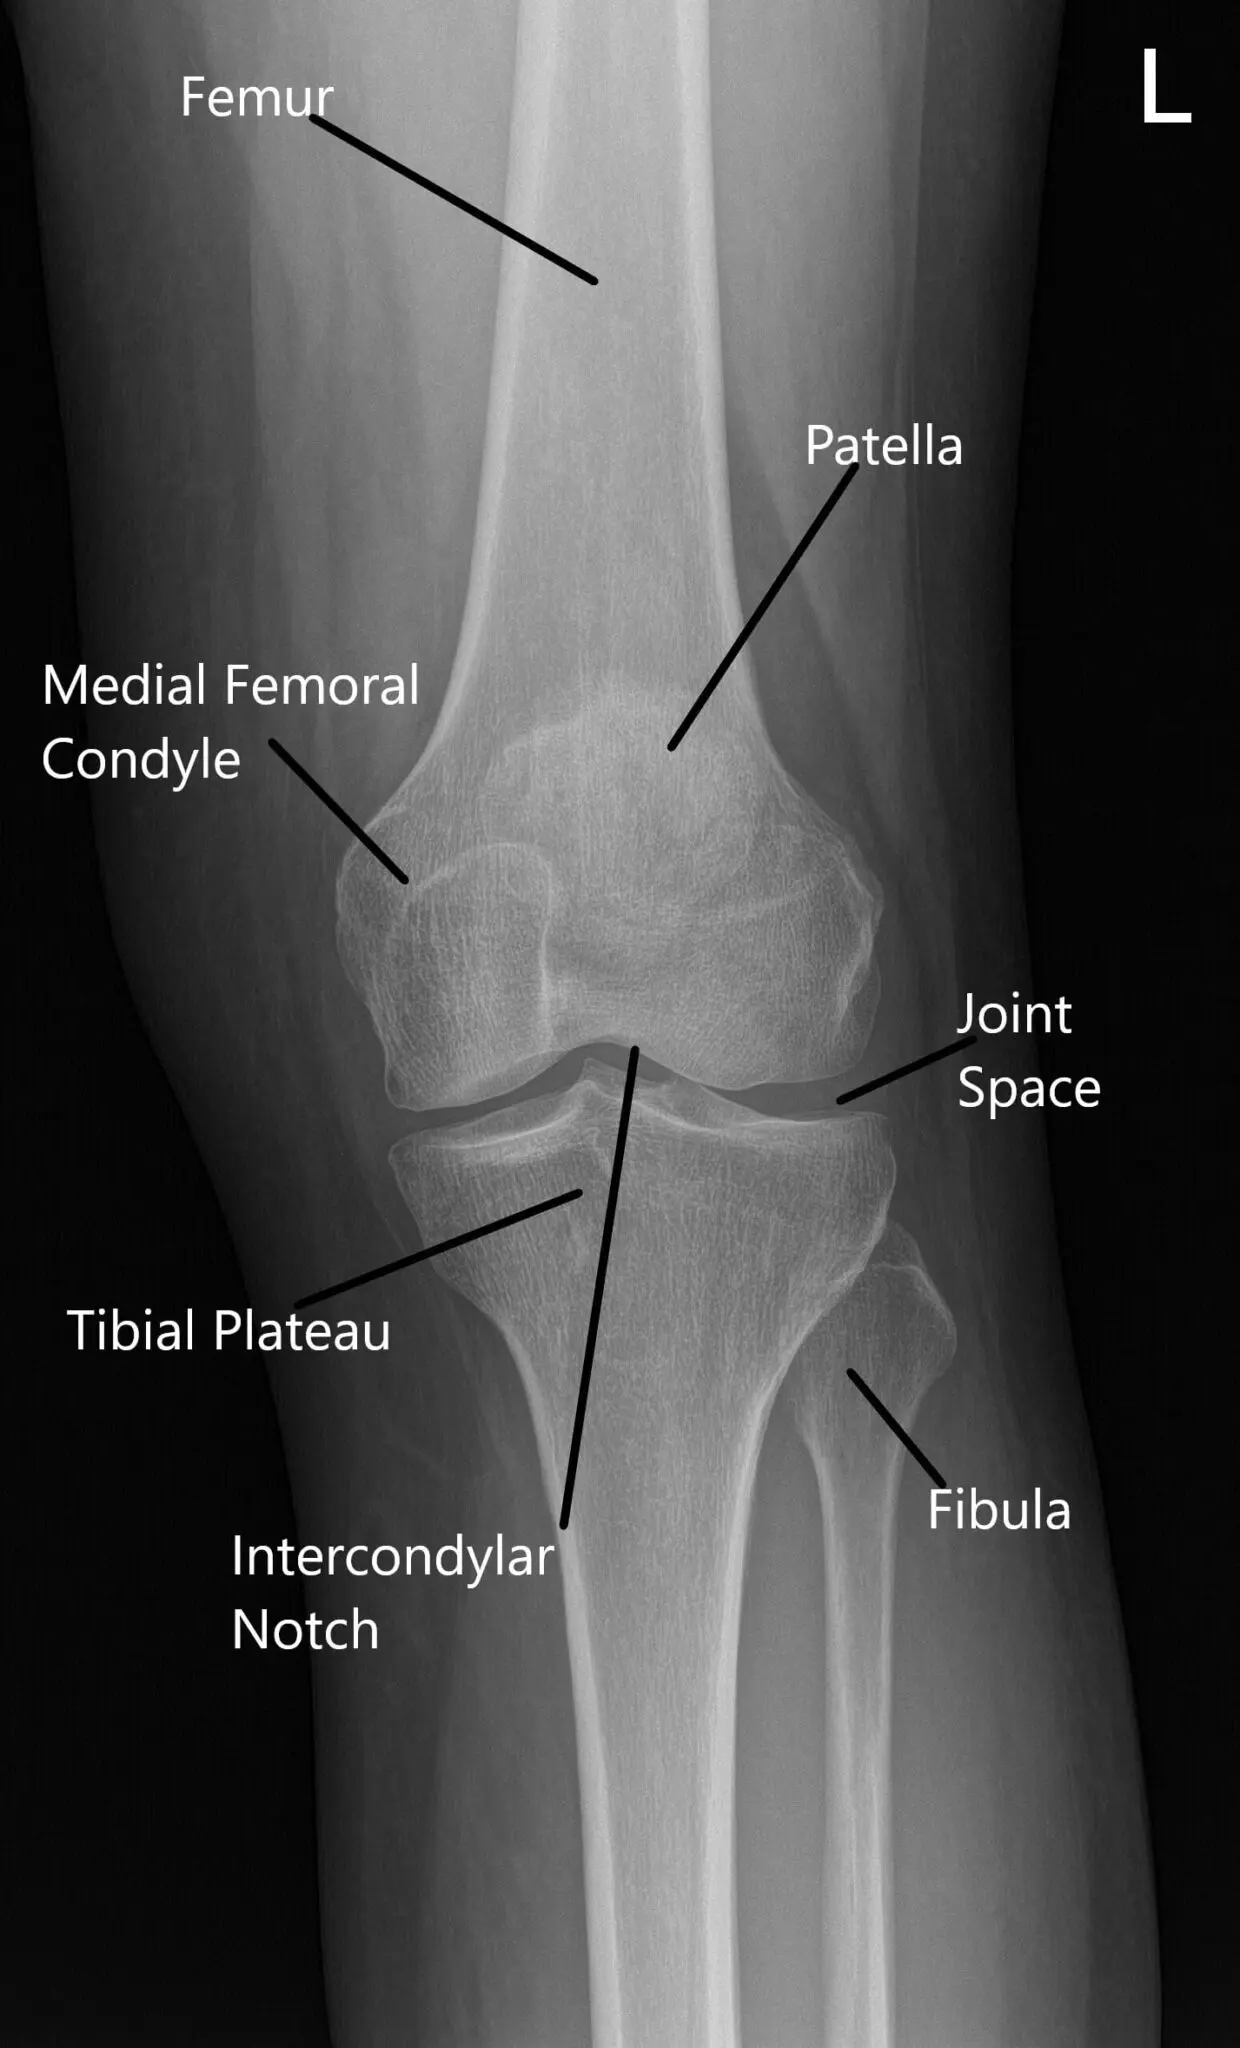

Imágenes de artroscopia intraoperatoria.

La rodilla fue examinada de nuevo. Se tomaron fotos artroscópicas. Se realizó condroplastia de la faceta rotuliana inferomedial y se tomaron imágenes. Se realizó una sinovectomía parcial de la canaleta femoral medial.